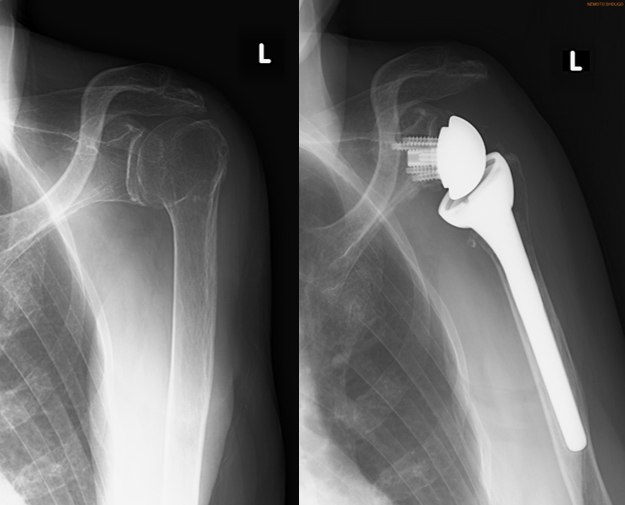

腱板断裂・変形性肩関節症・骨折の方が対象となり、腕の骨(上腕骨)と器の骨(肩甲骨)の凹凸に合った形のもの(人工肩関節)と、凹凸を逆転させた形のもの(リバース型人工肩関節)があります。両手術ともに大きな差はありません。

人工肩関節

【手術前レントゲン】 【手術後レントゲン】